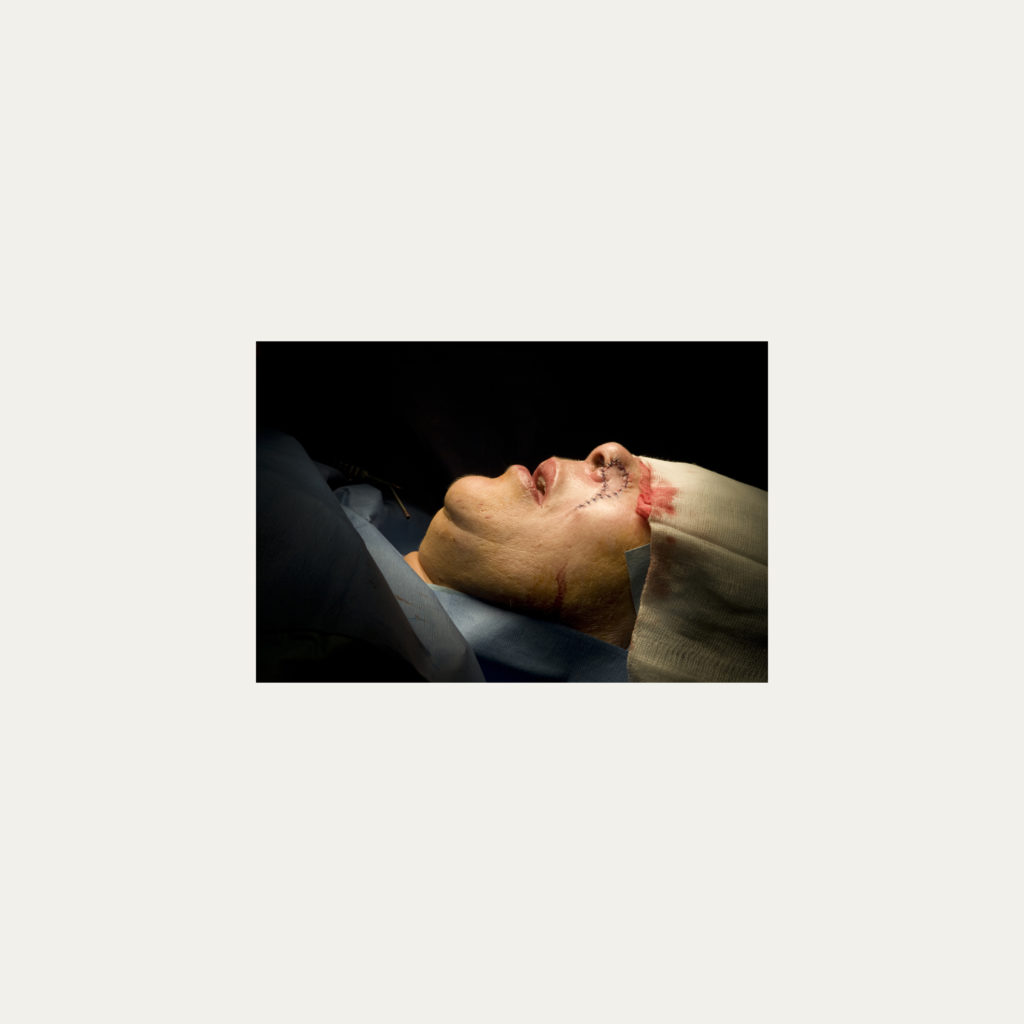

« Nature Morte » est la recherche de l’instant, pendant une intervention chirurgicale où la tête du patient opéré se retrouve seule dans le champ photographié. Aucune main intervenant, peu d’instruments chirurgicaux visibles, laissent le fragment de corps opéré existé pour lui-même. Les têtes, ainsi isolées, en deviennent presque des objets.

Cette approche est intensifiée par la présentation : dans de grands cadres carrés et passe-partout blancs, les photos de petit format font référence aux papillons épinglés de la collection d’un entomologiste.

Face à ces images, une forme de recueillement est nécessaire, s’approcher doucement pour s’approprier tous les détails des images.

Le caractère éminemment esthétique est souligné/donné par les gammes de couleur, la lumière précise sur la tête photographiée, les brillances partielles, renforçant également l’aspect pictural, les textures réelles.

L’humain présent dans ces images est celui qui rompt avec l’invisible et donne à voir l’architecture même de sa chair.